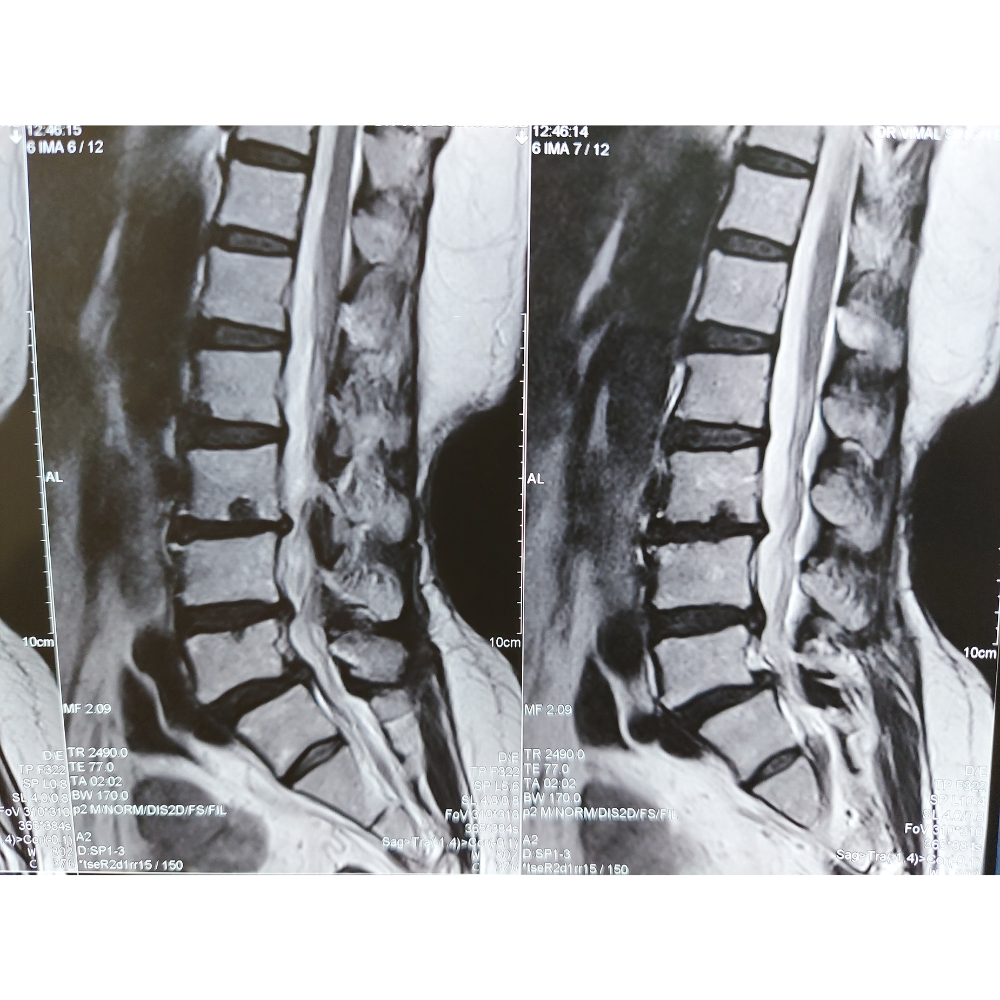

– Degenerative disc disease causing instability or nerve compression

– Lumbar spinal stenosis resulting in spinal canal narrowing and neurogenic claudication

– Spondylolisthesis, a condition where one vertebra slips forward relative to the one below it

– Recurrent disc herniation after previous discectomy surgery

– Spinal deformities such as scoliosis or kyphosis requiring fusion for stabilization